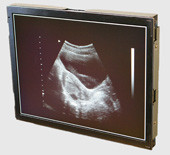

医療分野でも活躍する自社製品

省エネ部門と並んで力を入れているのが、市場として安定している医療分野。従来あるエコーなどの超音波診断画像を、自社の無線通信技術を使ってワイヤレスで遠隔にあるモニターに映し出すシステムだ。自社の持つ無線通信技術と超音波技術を融合させたもので、上田日本無線ならではの製品と言えるだろう。